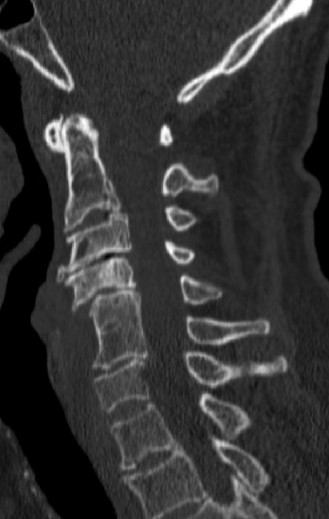

CASE 1 A 63-year-old male sustained a hyperextension injury to his neck while diving into a pool. Upon presentation, he reports decreased sensation in his hands and decreased strength in his arms and wrists, but no lower extremity complaints. On motor examination, he has 5/5 strength in his deltoids and elbow flexors and 4/5 strength in the elbow extensors, wrist extensors, and finger flexors. Lower extremity motor examination is normal. Sensation is decreased to light touch in both hands. Otherwise his sensation is preserved. Images of his cervical spine are shown in Figures 1–1 to 1–3.

Figure 1–1

The correct answer is (B). The clinical scenario describes a patient with central cord syndrome (CCS). CCS continues to be the most common incomplete spinal cord injury accounting for 15.7% to 25% of all spinal cord injuries. The characteristic presentation is an extension moment injury in a previously spondylotic and stenotic spine. Figures 1–1 to 1–3 demonstrate a spondylotic spine with central narrowing and CSF effacement that is worst at the C3–4 level. Bleeding, edema, and/or Wallerian degeneration lead to damage of the lateral corticospinal tract which is the main descending motor tract in the spinal cord. The more central anatomic position of the homunculus to the upper extremities places them at greater risk than those to the lower extremities. As such, injury to the lateral corticospinal tract is characterized by upper more than lower extremity involvement and motor deficits being more pronounced than sensory deficits.